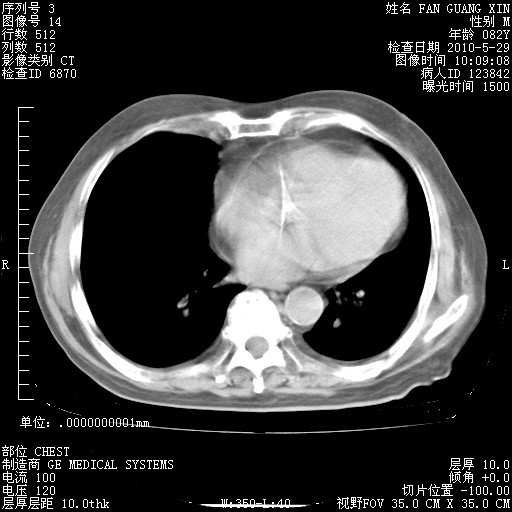

治疗3周后的肺部CT纵隔窗

从胸部影像学来看,的确有好转。至于目前为何发热不甚清楚?除了发热还有其他症状如有无喀痰,痰呈丝状吗?等等。尽量搜寻有无致发热其它可能原因?真菌?其它?如果的确无其他致发热的原因,考虑将甲强龙调至60-80mg bid/日。免疫全套基本无异常,考虑多系特发性肺间质纤维化

再治疗10天后的肺部CT

再治疗10天后的肺部CT 纵膈窗

阅读此次胸部CT,肺间质渗出性改变较入院时有吸收。目前从体温、白细胞、中性分叶明显增高,肯定存在细菌感染(发生医院感染哦,若无消化道及泌尿系统等感染的依据,肺部感染可能大)。若你院头孢哌酮舒巴坦钠耐药率较高,同意你的方案,若48小时体温仍高,可考虑使用碳青霉稀类抗菌药物,同时可予超声雾化、注意滴数时加大液体量。白蛋白33.30g/L较低哦,需加强营养等支持治疗。